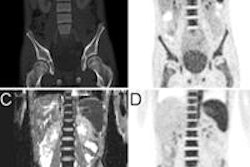

The researchers compared PET/CT and MRI to determine the extent of tumors and local and distant metastases. They then fused PET and pelvic MRI to assess nodal involvement using fusion software.

Five patients (28%) were upstaged based on hypermetabolic lesions seen on PET/CT; three moved from stage III to IV. Four patients (22%) were downstaged because lymph nodes identified on MRI were negative on PET. MRI and FDG-PET/CT examinations were concordant for the remaining nine patients (50%).

MRI provides "excellent anatomical evaluation" of tumor size and extent, while PET/CT offers additional information on metabolic activity, Gupta and colleagues concluded.

"Fusion PET/MRI can provide more accurate staging of local nodal involvement," they wrote in the study abstract. "This may change the initial stage, which can affect treatment options."